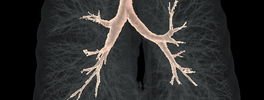

3D CT Trachea & Bronchus

Virtual Bronchoscopy